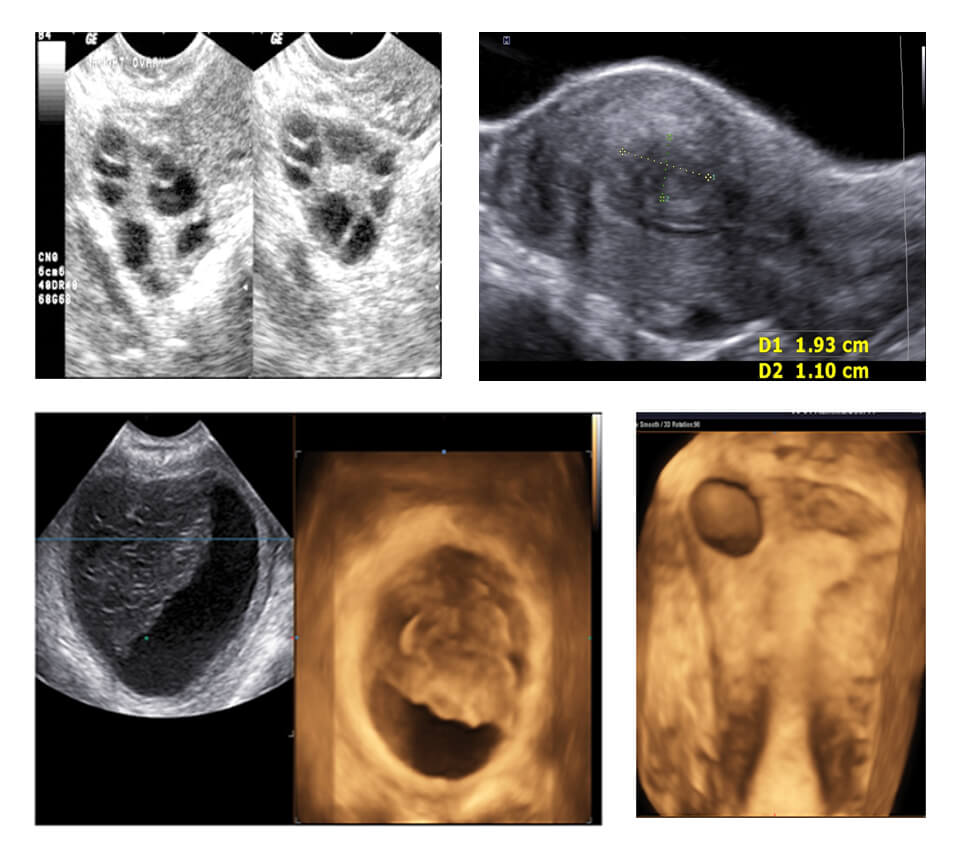

MODULE 2 :- GYNECOLOGY

NORMAL AND ABNORMAL : UTERUS (ENDOMETRIUM/MYOMETRIUM/ JUNCTIONAL ZONE), NORMAL AND ABNORMAL : ADNEXA (ENDOMETRIOSIS/ SIMPLE CYST/ PCO/ DERMOID/ MALIGNANCY), SCORING SYSTEMS IN GYNECOLOGY (MUSA/IDEA/IETA/IOTA)